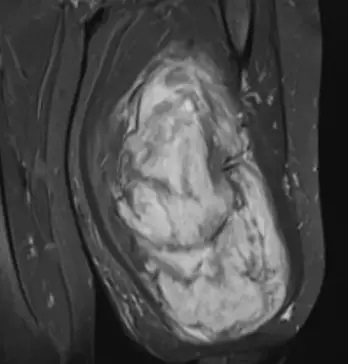

Muayenede yumuşak doku kitlesi olduğu değerlendirilen şişliğin alınması için Ortopedi ve Travmatoloji Anabilim Dalı Öğretim Üyesi Prof. Dr. Emin Özkul ve ekibi tarafından ameliyat kararı verildi. Yaklaşık 2 saat süren operasyonla kitlenin çıkarıldığı, kitlenin 5 kilo 668 gram geldiği belirtildi.

Bu hasta da 3 yıl önce fark edilmiş küçük bir kitle, zamanla çok büyük boyutlara, yaklaşık 6 kiloya varan boyutlara varmıştı. Neredeyse bütün bacak boyu yayılan bir kitlesi mevcuttu.

Kitlelerin görülmesi halinde sağlık kuruluşlarına başvurulması gerektiğini belirten Prof. Dr. Özkul, “Hastamızda yaklaşık olarak 3 yıl önce şikayetleri başlamış. Sonra zaman içerisinde hızla büyüyen bir kitleye sahipti. Şanslıydı ki herhangi bir sinirine zarar vermemişti. Hayatına fonksiyon bozukluğu olmadan devam edebilecek.

Bölgemize yaşayan ve ülkemizde yaşayan herkese şunu söylüyoruz. Küçük de olsa yumuşak doku kitlelerini önemsemeleri ve uzman görüşü almalarını öneriyorum. Bu hastadan 5 kilo 668 gramlık bir kitle çıkarttık. Bu benim mesleki yaşamım boyunca çıkarttığım en büyük kitlelerden bir tanesiydi.